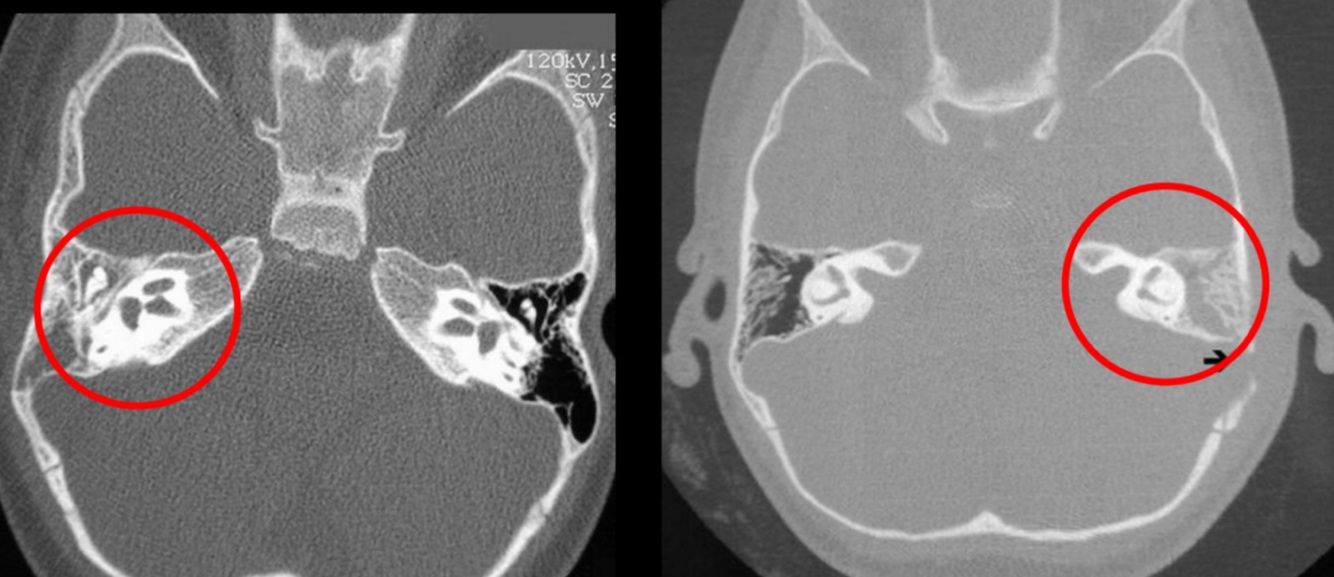

Mejor estudio de imagen para otitis media:

TC

Compara: no hay aire

Hallazgos de TC en otitis media:

• Masa bien definida en oídeo medio: densidad intermedia

• Erosiones osiculares

Asociado a mastoiditis